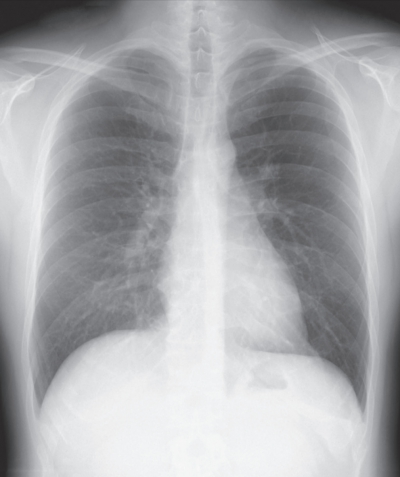

A 21-year-old previously healthy man presented to the emergency room with chest pain, which was worse on breathing, lasting for two days. Lung and heart examinations were unremarkable. Chest X-ray and ECG are shown in the figure.

What is the most likely diagnosis?